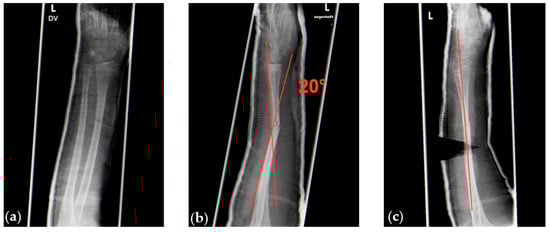

We performed radiographic controls 5 to 10 days after trauma and decided whether to perform cast wedging or not. Our indications for cast wedging followed the guidelines published by von Laer [1]. Furthermore, we decided to perform cast wedging also for angular deformities >20° in the sagittal plane in distal forearm fractures to prevent further displacement (Figure 8).

Figure 8. (a) Radiographic images of a sagittal 25° angular deformity of a dorsally displaced complete fracture of the distal radial metaphysis. (b,c) Angulation after cast wedging reduced by 15°, moving the deformity into the limits of sufficient spontaneous correction.